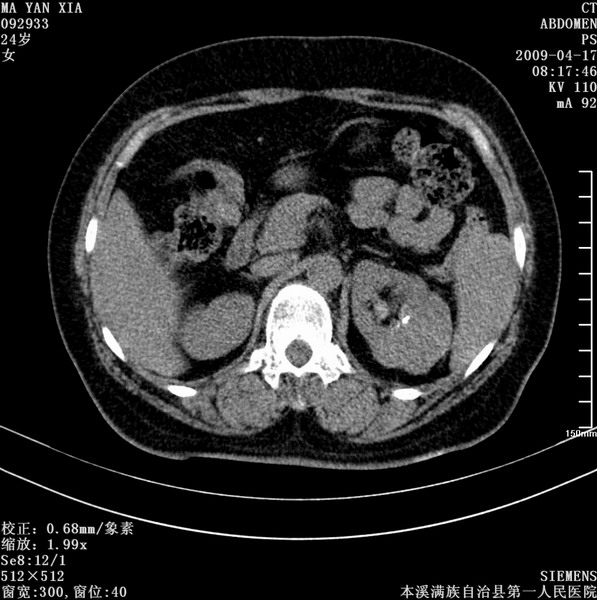

标题: CT19443:肾脏肿瘤两个区强化不一样。 [打印本页]

标题: CT19443:肾脏肿瘤两个区强化不一样。

女,51岁,体检时发现肾脏占位,建议ct增强。无任何自觉症状。

典型的不均匀强化,左肾癌

首先考虑肾癌,但如果术后病理是血管平滑肌脂肪瘤也不意外.